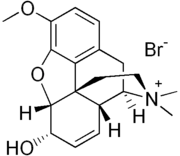

- Codeine methylbromide

Codeine methylbromide Codeine methylbromide |